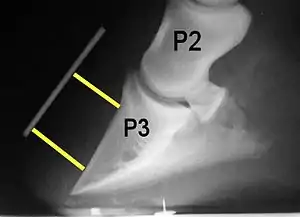

Radiograph of a horse hoof showing rotation of the coffin bone and evidence of sinking, a condition often associated with laminitis. The annotation P2 stands for the middle phalanx, or pastern bone, and P3 denotes the distal phalanx, or coffin bone. The yellow lines mark the distance between the top and bottom part of the coffin bone relative to the hoof wall, showing the distal (bottom) of the coffin bone is rotated away from the hoof wall.

Rotation is the most common form of displacement, and, in this case, the tip of the coffin bone rotates downward.[4] The degree of rotation may be influenced by the severity of the initial attack and the time of initiation and aggressiveness of treatment. A combination of forces (e.g. the tension of the deep digital flexor tendon and the weight of the horse) result in the deep digital flexor tendon literally pulling the dorsal face of the coffin bone away from the inside of the hoof wall, which allows the coffin bone to rotate. Also, ligaments attaching the collateral cartilages to the digit, primarily in the palmar portion of the foot, possibly contribute to a difference in support from front to back. The body weight of the animal probably contributes to rotation of the coffin bone. Rotation results in an obvious misalignment between PII (the short pastern bone) and PIII (the coffin bone). If rotation of the third phalanx continues, its tip can eventually penetrate the sole of the foot.